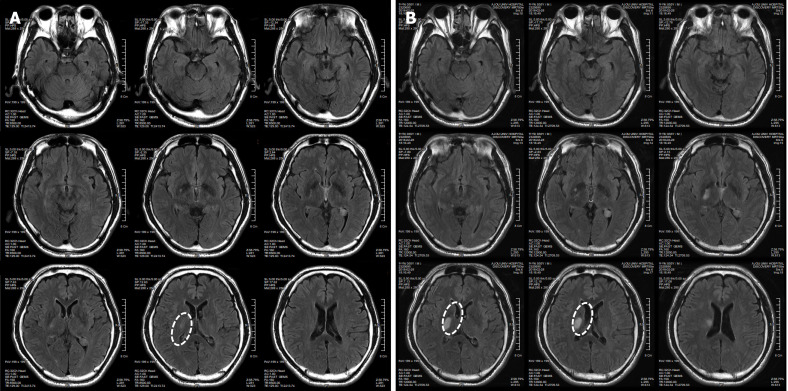

患者于2018年2月17日至18日出現暫時性無力癥狀,早上醒來后突發急性中風,導致左上肢和下肢癱瘓。患者在大學醫院急診室被診斷為Rt紋狀體囊性梗死(圖1A)。他于2018年3月2日出院,僅接受了阿司匹林處方,因為根據腦計算機斷層掃描 (CT) 掃描,他的腦血管正常,盡管他的病情在住院期間惡化(圖1)。出院當天,他被送往康復專科醫院接受長期康復治療。然后他于2018年3月13日來韓國首爾生物美容與健康公司 (bBHC)-干細胞治療與研究所 (STRI)接受干細胞治療。

患者在干細胞移植后約30個月拍攝腦部CT圖像以確認病灶的大小。病灶縮小至0.6cm×0.3cm(圖4)。